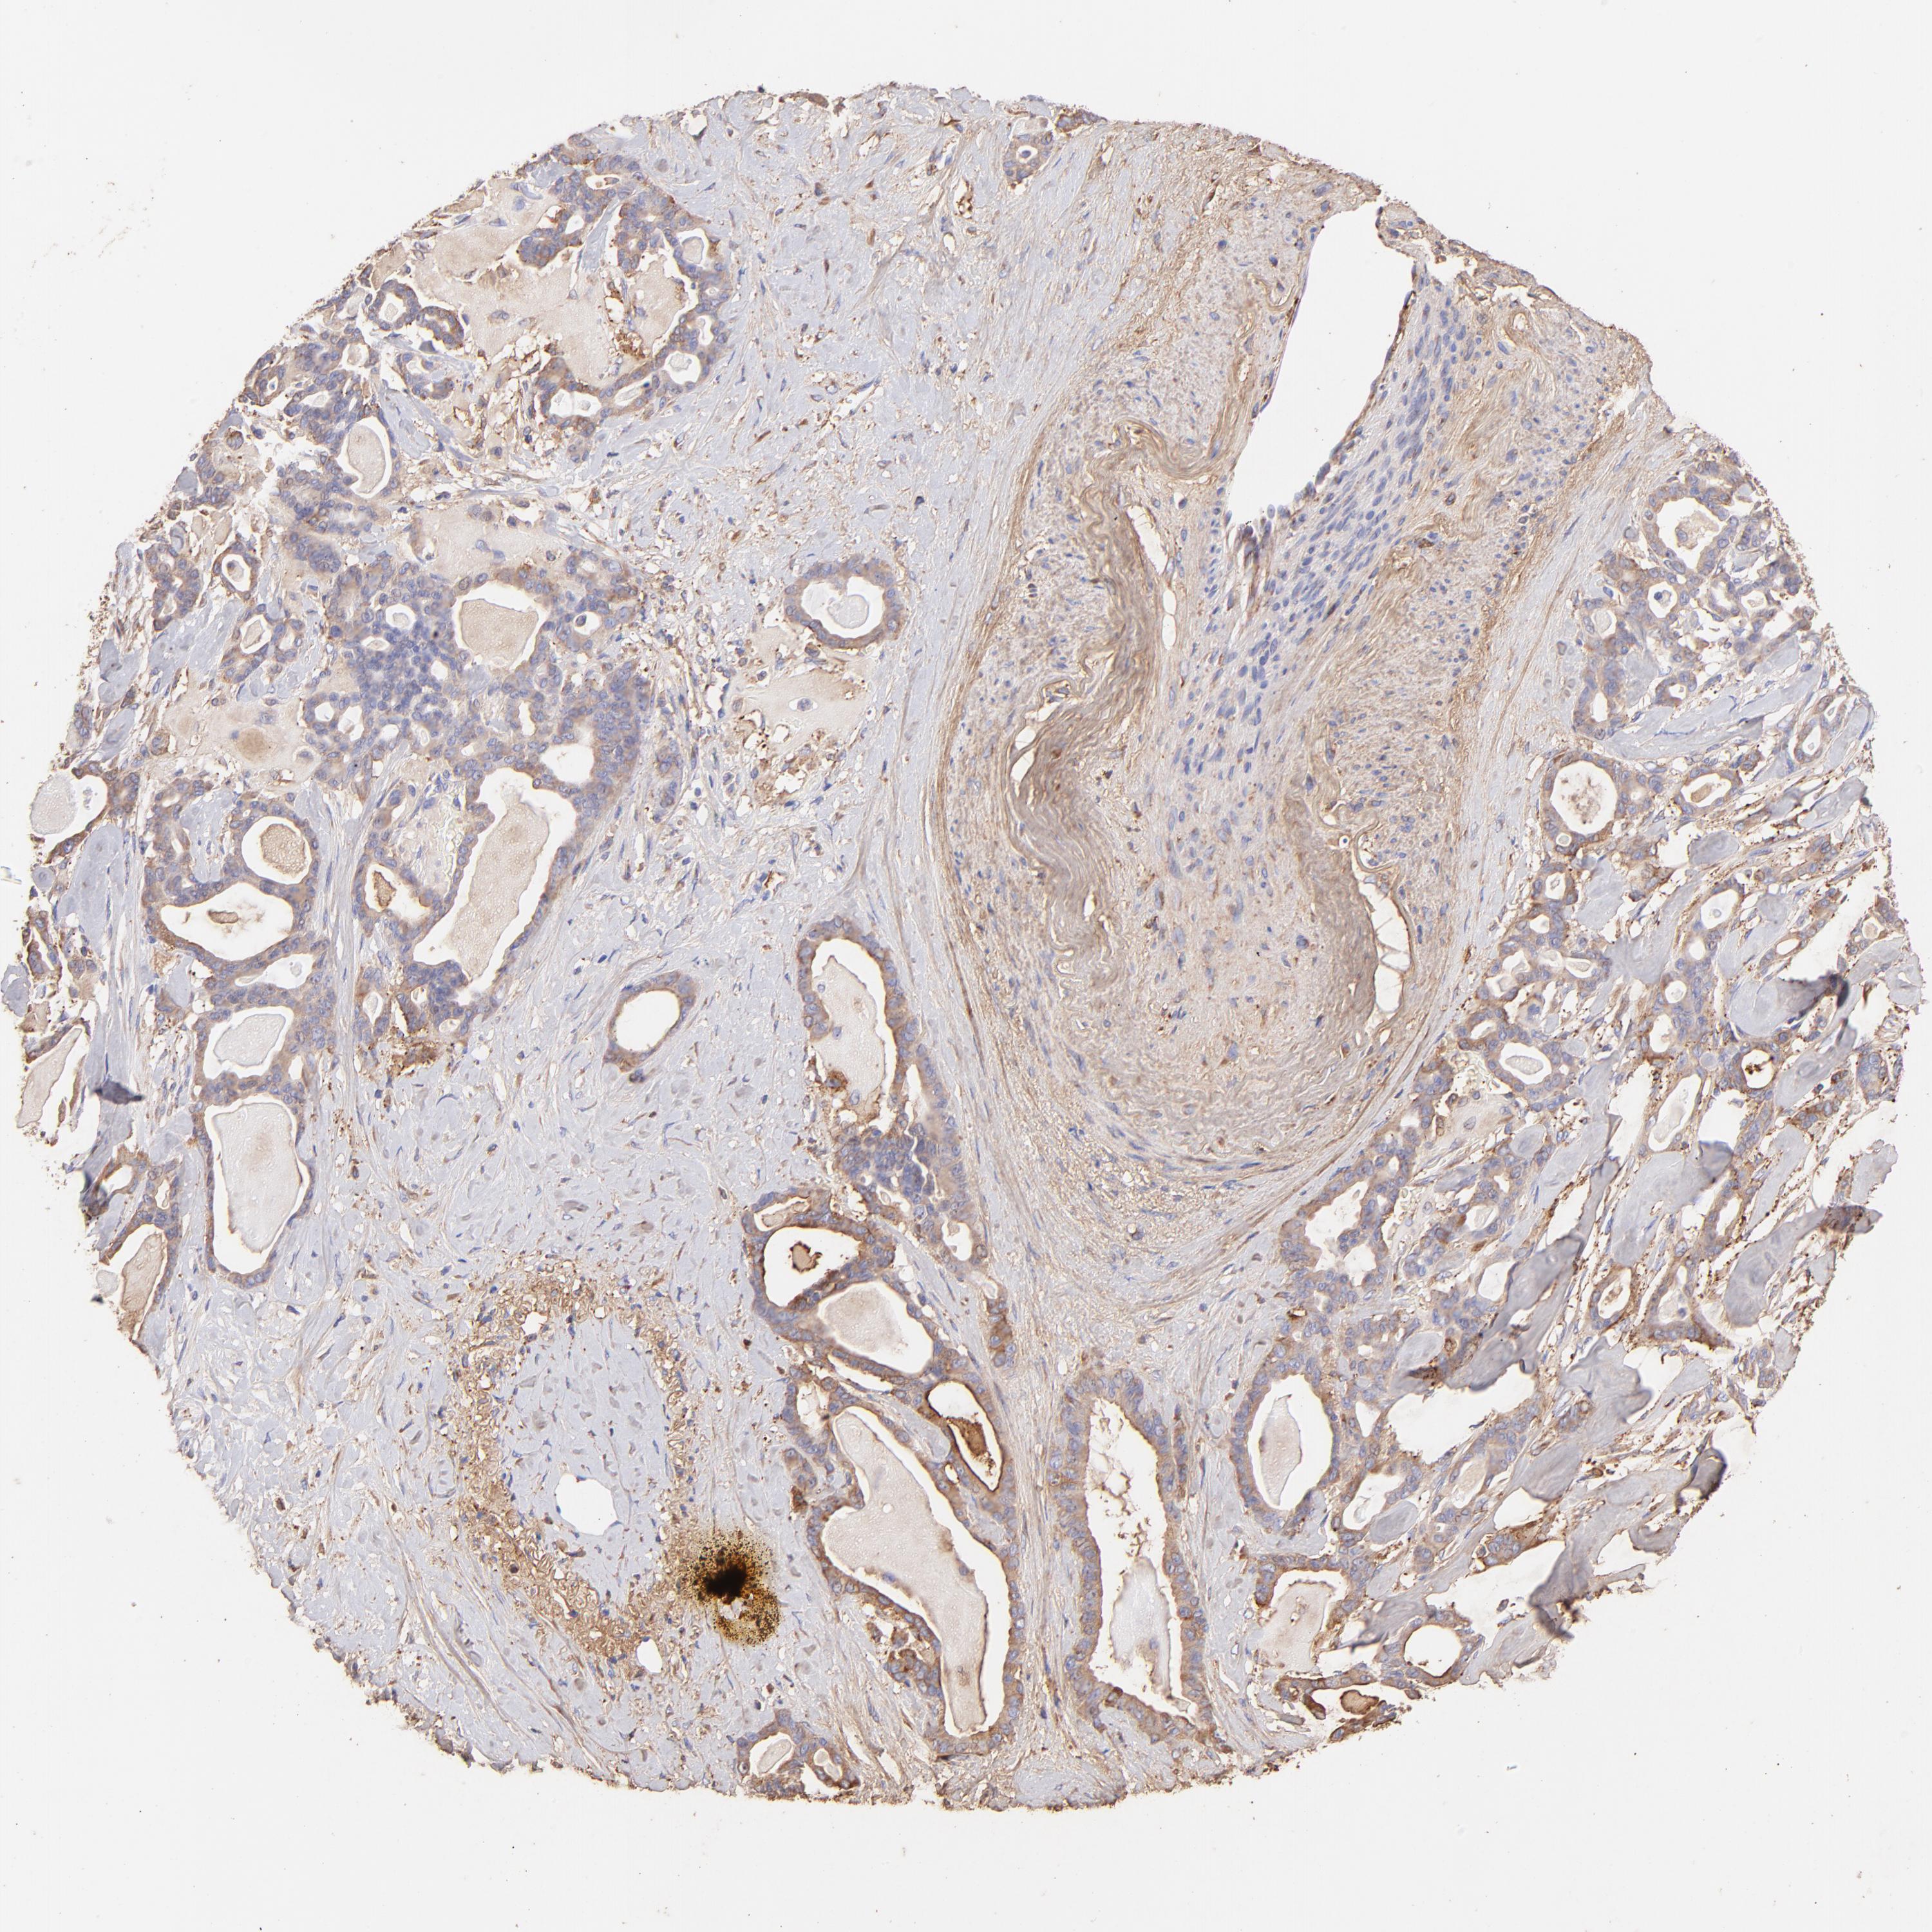

PANCREATIC CANCER - Protein expressioni

A mouse-over function shows sample information and annotation data. Click on an image to view it in a full screen mode. Samples can be filtered based on level of antibody staining by selecting one or several of the following categories: high, medium, low and not detected. The assay and annotation is described here.

Note that samples used for immunohistochemistry by the Human Protein Atlas do not correspond to samples in the TCGA dataset.

Antibody stainingi

Antibody staining in the annotated cell types in the current human tissue is reported as not detected, low, medium, or high, based on conventional immunohistochemistry profiling in selected tissues. This score is based on the combination of the staining intensity and fraction of stained cells.

Each image is clickable and will lead to virtual microscopy that enables deeper exploration of all samples and also displays staining intensity scores, fraction scores and subcellular localization as well as patient and tissue information for each sample.

Antibody HPA003157

Antibody CAB003678

Staining

High

Medium

Low

Not detected

Intensity

Strong

Moderate

Weak

Negative

Quantity

>75%

75%-25%

<25%

None

Location

Nuclear

Cytoplasmic/membranous

Cytoplasmic/membranous,nuclear

Adenocarcinoma, NOS

Adenocarcinoma, metastatic, NOS